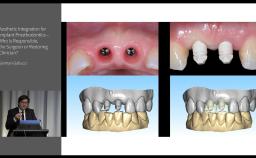

German Gallucci